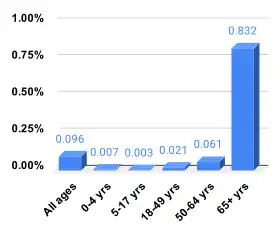

People who are at least 65 years of age,[9] due to a weakened immune system from aging or a chronic illness, are a high-risk group for developing complications, as are children less than one year of age and children who have not been previously exposed to influenza viruses multiple times. Pregnant women are at an elevated risk, which increases by trimester[1] and lasts up to two weeks after childbirth.[9][32] Obesity, in particular a body mass index greater than 35–40, is associated with greater amounts of viral replication, increased severity of secondary bacterial infection, and reduced vaccination efficacy. People who have underlying health conditions are also considered at-risk, including those who have congenital or chronic heart problems or lung (e.g. asthma), kidney, liver, blood, neurological, or metabolic (e.g. diabetes) disorders,[8][1][9] as are people who are immunocompromised from chemotherapy, asplenia, prolonged steroid treatment, splenic dysfunction, or HIV infection.[9] Current or past tobacco use also places a person at risk.[32] The role of genetics in influenza is not well researched,[1] but it may be a factor in influenza mortality.[11]

Influenza is typically characterized by seasonal epidemics and sporadic pandemics. Most of the burden of influenza is a result of flu seasons caused by IAV and IBV. Among IAV subtypes, H1N1 and H3N2 currently circulate in humans and are responsible for seasonal influenza. Cases disproportionately occur in children, but most severe causes are among the elderly, the very young,[1] and the immunocompromised.[4] In a typical year, influenza viruses infect 5–15% of the global population,[3][39] causing 3–5 million cases of severe illness annually[1][2] and accounting for 290,000–650,000 deaths each year due to respiratory illness.[3][4][44] 5–10% of adults and 20–30% of children contract influenza each year.[17] The reported number of influenza cases is usually much lower than the actual number of cases.[1][34]

During seasonal epidemics, it is estimated that about 80% of otherwise healthy people who have a cough or sore throat have the flu.[1] Approximately 30–40% of people hospitalized for influenza develop pneumonia, and about 5% of all severe pneumonia cases in hospitals are due to influenza, which is also the most common cause of ARDS in adults. In children, influenza is one of the two most common causes of ARDS, the other being the respiratory syncytial virus.[13] About 3–5% of children each year develop otitis media due to influenza.[8] Adults who develop organ failure from influenza and children who have PIM scores and acute renal failure have higher rates of mortality.[13] During seasonal influenza, mortality is concentrated in the very young and the elderly, whereas during flu pandemics, young adults are often affected at a high rate.[11]